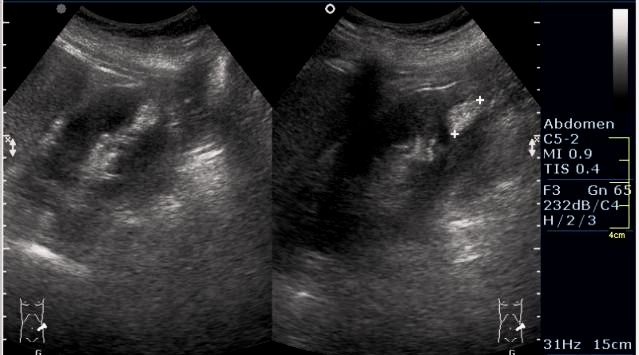

Женщина 50 лет. Жалоб нет. Обследование перед поездкой в санаторий по поводу дисфункции гепатобилиарной системы.

Случайная находка в нижней трети левой почки (не в полюсе, а по задне-медиальной поверхности).

Образование в левой почке

ПО УЗ-семиотике образование соответствует ангиомиолипоме (AML). По правилам в таких случаях необходимо выполнить КТ, доказать преимущественно жировой состав опухоли, затем проводить УЗ-наблюдение.

Согласен. Именно с таким диагнозом (ангиомиолипома) отправил на КТ. Особенностью случая ИМХО является заметный "выход" образования за контур почки (на 2/3 объема).

При ультрасонографии ангиомиолипома выглядит как округлое образование без капсулы с однородной внутренней эхоструктурой и четкими контурами; эхогенность ее чаще всего равна или чуть выше эхогенности перинефральной клетчатки [7]. Значительно реже эхогенность ангиомиолипом может быть равна эхогенности почечной паренхимы; такие опухоли состоят почти полностью из гладкомышечной ткани [8]. Иногда позади ангиомиолипомы может определяться слабая акустическая тень.